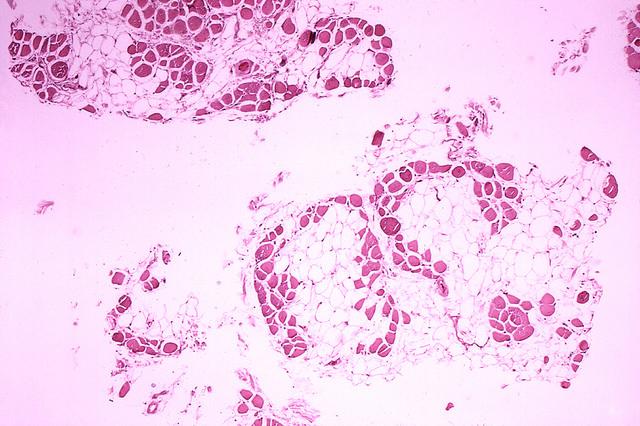

杜氏肌營(yíng)養(yǎng)不良癥患者的肌肉

科學(xué)家認(rèn)為,由于肌肉在DMD中不斷受損,衛(wèi)星細(xì)胞的修復(fù)負(fù)擔(dān)如此之大,以至于它們變得精疲力盡,失去了自我復(fù)制的能力。衛(wèi)星細(xì)胞對(duì)肌肉修復(fù)至關(guān)重要,因此隨著這些細(xì)胞數(shù)量的減少,肌肉的自我修復(fù)能力會(huì)越來(lái)越差。相反,受損的肌肉纖維會(huì)被脂肪細(xì)胞和疤痕組織所取代,從而削弱肌肉,直到它無(wú)法再有效地工作。

Emma Kemp 使用Servier Medical Art制作的肌肉結(jié)構(gòu)主圖和說(shuō)明 iPS 細(xì)胞在肌營(yíng)養(yǎng)不良癥細(xì)胞療法研究中的應(yīng)用?。Edwin P. Ewing, Jr 博士拍攝的杜氏肌營(yíng)養(yǎng)不良癥患者的肌肉圖像,由美國(guó)衛(wèi)生與公眾服務(wù)部公共衛(wèi)生圖像庫(kù)提供?。Mike Kayser的肌纖維照片?,Wellcome Images。?